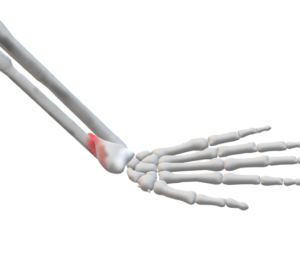

1. コーレス骨折

(発生)

介達外力が多い

手掌をついて転倒し、手関節に強度の伸展力が強制されて受傷

※橈骨遠位端部に掌側凸の屈曲力が働き、この際に前腕遠位端部に過度回外の捻転力が加わる

➀骨折線

前額面:橈側近位から尺側遠位

矢状面:手関節の1~3cm近位の手掌から、やや斜め背側近位に走る

➁転位

・背側転位

・橈側転位

・短縮転位

・捻転転位